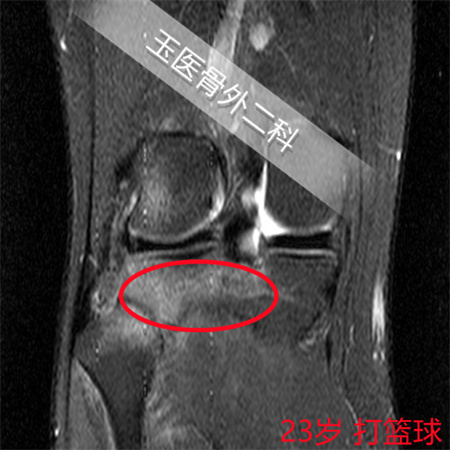

疲劳性骨折是由于持续性应力导致,在发生后,首先需要解决的就是减少导致疲劳性骨折发生的诱因。在治疗疲劳性骨折时,骨外二科运动损伤门诊的医生们,会采取阶梯性治疗方案:在早期,通过X片检查没有骨折线、核磁共振检查主要是大片集中的骨挫伤或者又称为隐性骨折的情况,以减少运动强度和运动时间为主,特别是对于初三学生,面临中考体育100分的目标,如果完全停止训练几个月后,前期的运动效果会很快退缩,这种情况,往往建议减少运动强度、缩短运动持续时间,同时间辅助局部冷敷,适当服用布洛芬的解热镇痛药物缓解肿痛,并补充钙剂、外用云南白药气雾剂等促进创伤修复药物。对于核磁共振已经显示裂纹骨折线,但还没有完全骨折,需要暂停跑步、并扶拐保护下行走,避免崴脚扭伤,下楼梯时需要缓慢,蹲起动作需要扶栏杆,避免损伤部位突然出现应力集中导致骨折完全移位,除了前面治疗方法外,还需要加上促进骨折愈合药物治疗。对于已经完全骨折并错位的骨折,尤其是不稳定性骨折,只有进行骨折的复位固定了。对于疲劳性骨折已经很长一段时间,X片显示已经有骨痂生长时,仅需要减少运动强度和缩短运动时间即可。